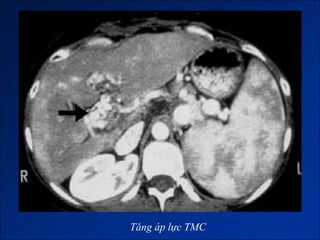

Tăng áp lực TMC

Dấu hiệu tăng ALTMC

2. Dấu hiệu tăng ALTMC